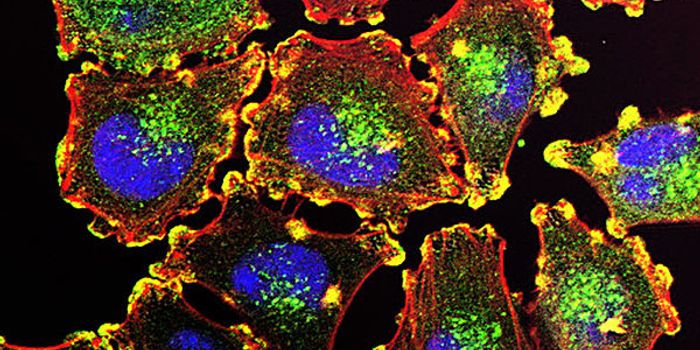

APR 24, 2015Cell & Molecular BiologyResearchers from the Universitat Autònoma de Barcelona (UAB) Department of Cellular Biology, Physiology, and Immunology, ...

DEC 19, 2015ImmunologyDendritic cells use phagocytosis to break up molecules from pathogens to present on their cell surface to warn other lym ...